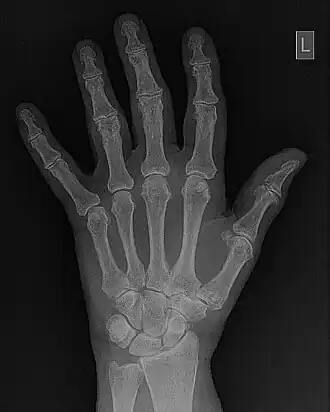

- Contrast Enhancement is a widely-used form of image processing used throughout medical imaging and will be used as an example of basic methods. This form of processing (commonly referred to as Windowing) is described below and is a form of grey-level transformation where the real pixel value is replaced by a new pixel value for display purposes. The process is generally performed using the Output Look- Up Table section of the image display component - see Figure 5.2. As a result, the original data in image memory is not affected by the process, so that from an operational viewpoint, the original image data can be readily retrieved in cases where an unsatisfactory output image is obtained. In addition, the process can be implemented at very high speed using modern electronic techniques so that, once again from an operational viewpoint, user-interactivity is possible.

- An example of a Look-Up Table (LUT) which can be used for contrast enhancement is illustrated in Figure 5.5. The process is controlled typically by two controls on the console of the digital image processor - the Level and Window. It should be noted that variations in the names for these controls, and in their exact operation, can exist with different systems but the general approach described here is sufficient for our purposes. It is seen in the figure that the level controls the threshold value below which all pixels are displayed as black and the window controls a similar threshold value for a white output. The simultaneous use of the two controls allows the application of a gray-level window, of variable width, which can be placed anywhere along the gray scale. Subtle gray-level changes within images can therefore be enhanced so that they are displayed with greater clarity - see Figure 5.6.

- Contrast enhancement can also be effected through manipulation of the image's statistical histogram and is illustrated in Figure 5.8. A histogram is a plot of the frequency of occurrence of each pixel value in an image - see panel (a) for an example, where this frequency is plotted as a function of pixel value. It can be seen that pixels from the black surroundings of the hand are indicated by the peak at low pixel values. It can also be seen that the pixel values representing bone and tissue attenuation form a broad range of lower frequencies extending to just over half the grey scale. Indeed the pixels of the 'L' marker can be seen to form an isolated blip at a pixel value of 75. Note that the term frequency as used here should not be confused with the term spatial frequency we have been using in our discussion of Fourier techniques.

- Fourier filtering is illustrated in more detail in Figure 5.10. The wrist/hand radiograph of the Figure 5.6 is again used for this illustration. You might remember that its 2D FFT was discussed in an earlier chapter. The filter is shown in panel (c) of the figure in the form of a two-dimensional image. It can be seen that the image data is symmetrical around the centre (i.e.isotropic) where its pixel values are relatively low. Outside this central dark region, a halo of bright pixel values dominates the image as the pixel value trails off slowly towards the periphery. An amplitude profile through this image is shown in panel (d) to further illustrate the effect. The filter can be used to modify the 2D-FFT by multiplying it by the filter values, for instance, to form a filtered 2D-FFT - as shown in panel (e). The Inverse FFT (IFT) of this data is then reveals the filtered image - see panel (f). Given that certain spatial frequencies have been amplified while others have been suppressed with this type of filter, it is called a Bandpass filter.